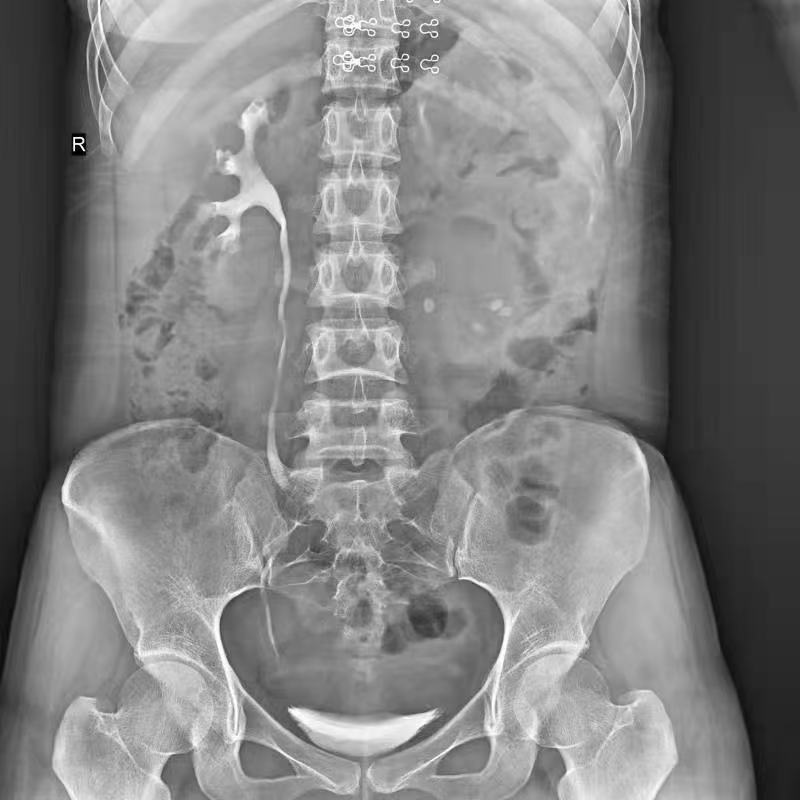

普利德醫(yī)療自主研發(fā)的新一代數(shù)字化X線透視攝影系統(tǒng),可應(yīng)用于DR攝影、數(shù)字透視、數(shù)字造影以及可視化精準(zhǔn)DR拍片等多種臨床X線檢查領(lǐng)域。

球管傾斜攝影角度-45°~45°,滿足臨床各部位各角度的攝影需求。如:髕骨軸位、頸椎正位、骶尾椎、鼻竇瓦氏位、梅氏位等部位檢查。

拉伸自如:SID電動(dòng)拉伸,最長(zhǎng)可延伸至1.8米,滿足放射科室各種拍片距離的需求。如:GBZ 70-2015職業(yè)性塵肺病的診斷標(biāo)準(zhǔn)中對(duì)胸片拍片距離1.8米的要求。